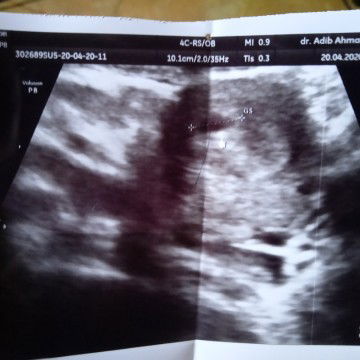

hamil pertam

Apakah normal timbul flek coklat saat hamil 6 Minggu?